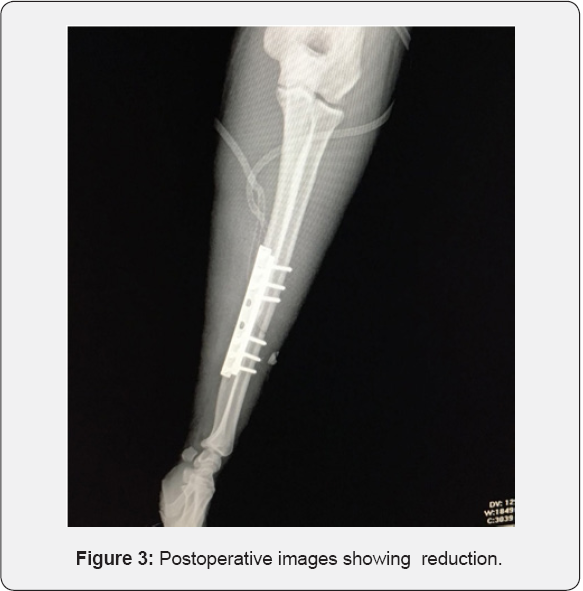

Internal fixation of the radius was done with an 6-hole 3.5mm dynamic compression plate (DCP) using the volar approach of Henry. Similarly, ulna was fixed with 8-hole 1/3 tube from dorsal approach. Postoperative radiographs demonstrated satisfactory reduction of the fractures and the elbow dislocation (Figure 3 & 4).